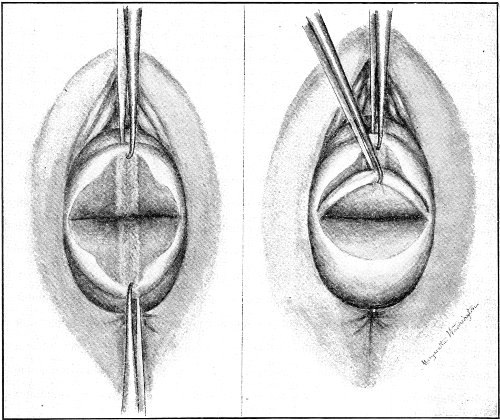

Slight Median laceration of the Perineum.—In this injury the tear takes place through the fourchette. Posteriorly it may extend as far as the sphincter ani muscle. Upward it may extend for an inch up the posterior vaginal wall. The appearance of this tear is shown in Fig. 33. It will be noted that, as this tear takes place in the median line, none of the muscles that support the perineum are involved, nor are the planes of fascia injured. The perineum is slightly split, and the insertions and origins of the muscles and the fascia are slightly separated. The supporting structures of the perineum and the pelvic floor are, however, uninjured.

Fig. 33.—Recent slight median laceration of the perineum: sutures introduced.

If this tear is detected after labor, it should be closed by the immediate operation. A slight tear involving chiefly the cutaneous aspect of the perineum should be closed by three or four sutures introduced from the outside, as in Fig. 33. The needle should be introduced about a quarter of an inch from the edge of the wound. It should not be passed parallel with the plane of the lacerated surface, but should be swept outward and then inward toward the 68 angle at the bottom of the tear (Fig. 34). It may either emerge at the angle and be re-introduced, or it may be passed directly through to the skin-margin on the opposite side of the wound. If the suture is passed in this way, there will be perfect apposition throughout the whole surface of laceration. If the sutures are improperly passed, there may result only apposition of the skin-edges.

Fig. 34.—Diagram representing the correct and the incorrect method of passing the suture for closure of slight perineal laceration.

If the laceration extends up the posterior vaginal wall, two sets of sutures must be introduced—one on the vaginal aspect of the tear, and one on the skin aspect (Fig. 35).